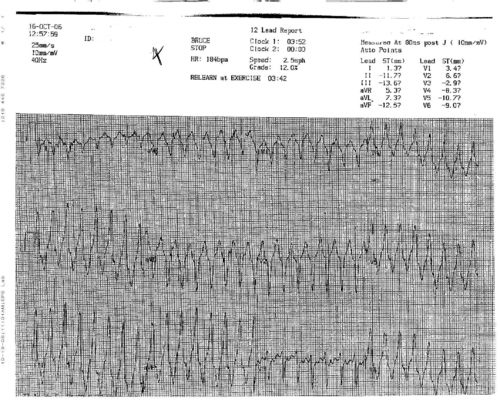

EKG

EKG Localization